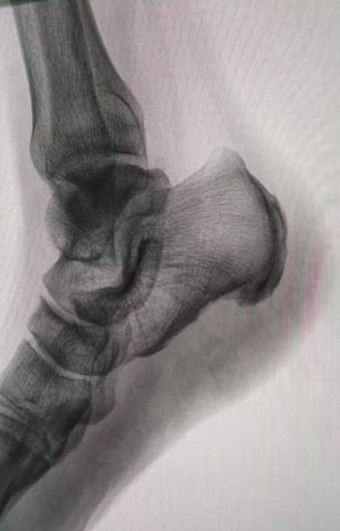

为了解决这个难题,我院足踝外科的医生们一直专研微创技术,还结合了国内外最先进的治疗经验,终于研究出了关节镜微创治疗的好方案。这个技术最大的好处就是伤口小、定位准、好得快:只需要在脚后跟骨头上开个约0.5厘米的小口,通过关节镜的高清镜头,直接找到病根。医生能清楚地看到发炎的部位,精准松解筋膜,清理掉发炎的坏组织;如果脚后跟还有骨刺,也能一起磨掉,从根儿上解决疼痛的问题。

这次做手术的患者,被足跟痛折磨了一年多,做了6个多月的保守治疗都没效果,正常生活都受大影响了。团队专门为他定制了手术方案,术前仔细做了检查、评估了身体状况,手术过程特别顺利。术后第二天,患者就在医生护士的指导下下床慢慢活动了,足跟的刺痛感明显减轻;伤口恢复得也特别好,没有渗血渗液,没多久就顺利出院了。复查的时候,患者的足底疼痛完全消失了,能正常走路、运动。